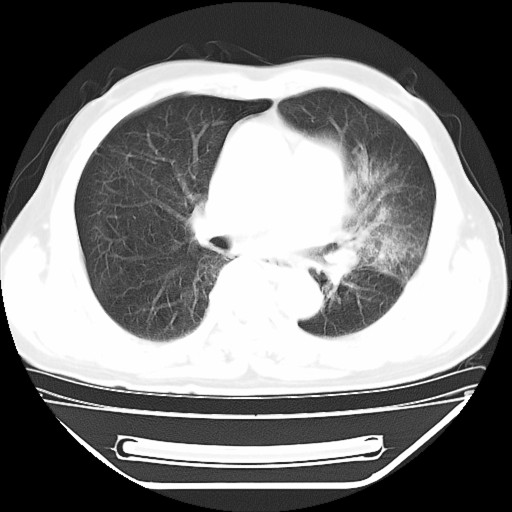

以下是引用hhcckk在2009-5-29 10:34:00的发言:[br]左下肺片絮状边缘模糊影,考虑感染,建议治疗后复查[br]